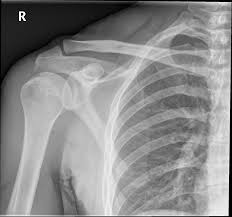

This 1 day seminar is aimed at MSK professionals with an interest in the imaging of the shoulder. The seminar will be delivered by Chiropractic Radiologists and a Medical Anatomist.

Anatomy of the shoulder will be detailed using plain film x-ray, MRI and ultrasound imaging, backed up by a practical session in the on-site pro-section lab.

The radiologists will cover the clinical indications for each imaging modality, normal imaging series and measurements, reporting terminology and indicators of pathology and trauma.

- Recognise normal anatomical appearance of the shoulder on x-ray and MRI